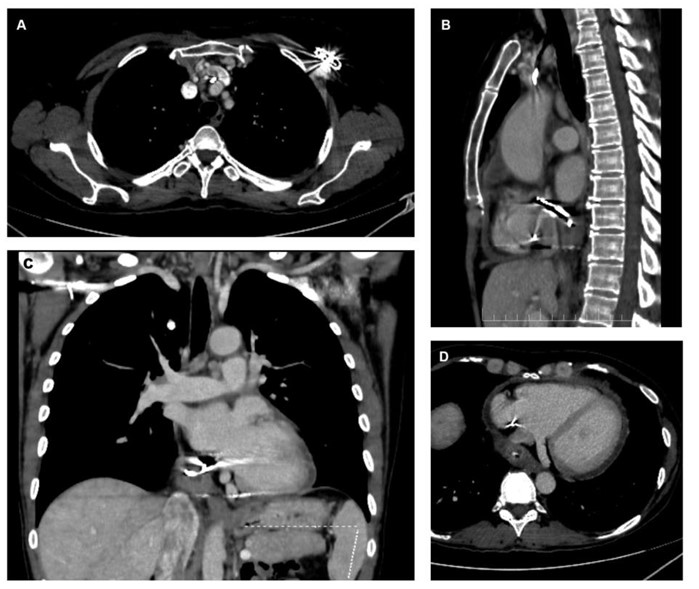

Fig. (2).

Contrast-enhanced CT scan showing (A) axial view of the pacemaker generator area with venous thrombus adjacent to the leads, (B) sagittal view with extravascular lead trajectory, (C) coronal view of the abscessed area in the pericardial sac, and (D) axial view showing the relationship of the abscess to the coronary sinus and inferior vena cava.

The patient was subsequently admitted to the Internal Medicine Department, and a contrast-enhanced computed tomography (CT) of the body was performed. The scan revealed that the atrial lead of the pacemaker traversed the inferoposterior wall of the RA. The lead tip appeared to be located within the pericardial sac, surrounded by a centimeter-sized fluid collection suggestive of abscess formation (Fig. 2A-D). The vena cavae were dilated, and the pericardium demonstrated mild enhancement and effusion suggestive of probable pericarditis.